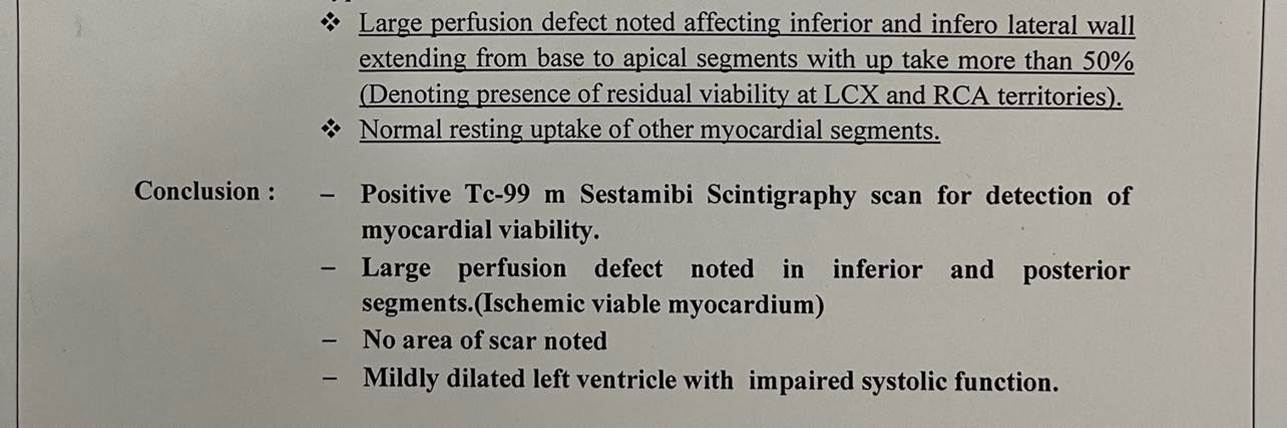

Coronary angiography was done showing patent previous LAD stent and CTO RCA ** Symptomatic patient ** Good EF with SWMA at RCA territory ** Recurrent admissions with ACS And also Thallium study was done to document Ischemic burden of RCA territory and was positive